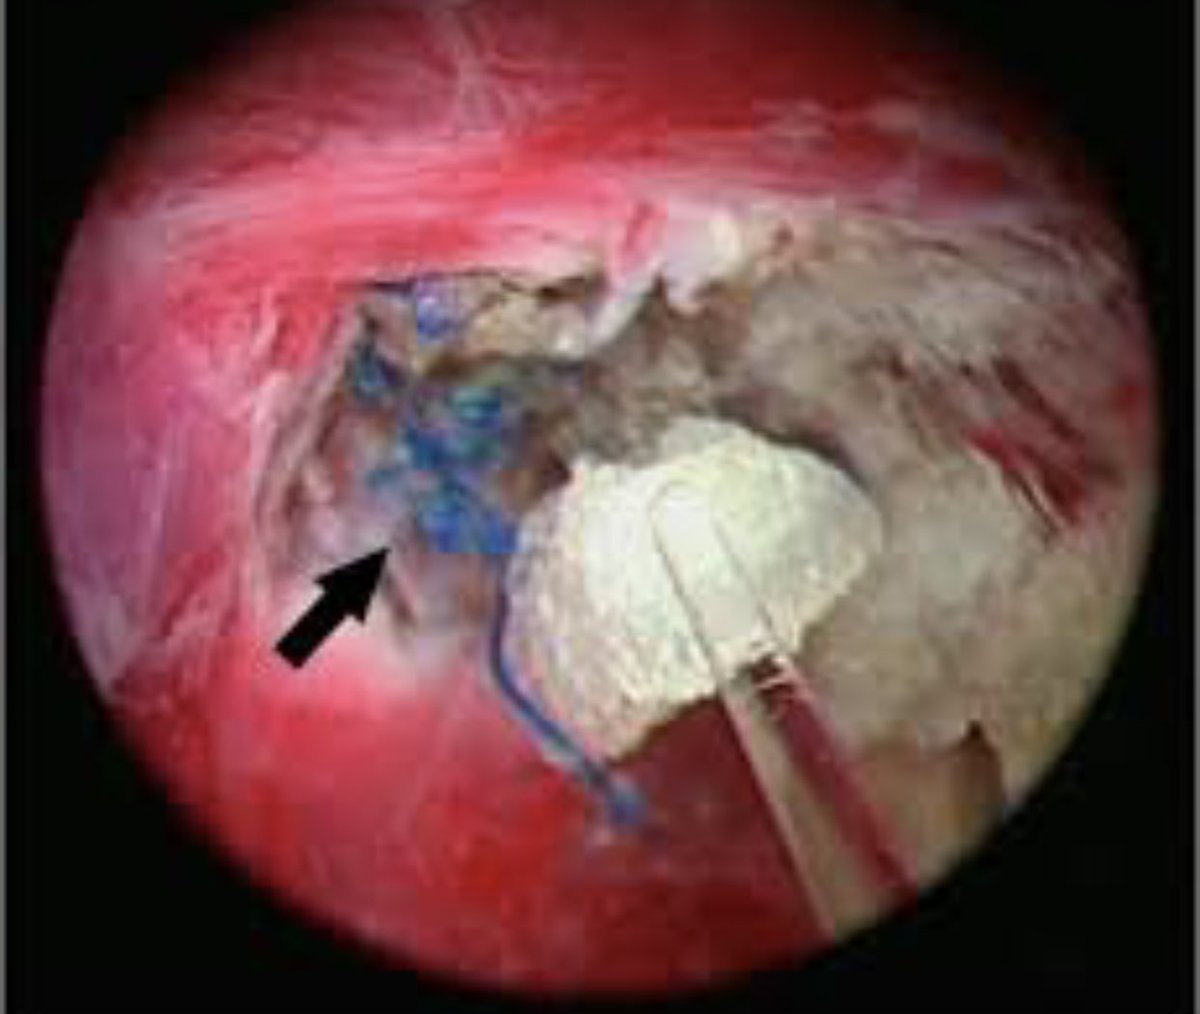

Lead at Glasgow Mesh Centre is ambushing patients before surgery to talk them into a new ‘softer mesh.’ Who is looking out for patients? Who gains out of this? Certainly not us!! Does she?? Humza Yousaf NHS Greater Glasgow and Clyde Michael Matheson MSP @MarGarland16 mazk 🏴 Gillian Watt #mesh

This is OUTRAGEOUS 🤬 When will they bloody well learn that #mesh #maims 😭😭 Lucy Adams Brendan O'Hara MP Patient Safety Commissioner @MBLacey Jackson Carlaw Prof Sir Gregor Smith First Minister Jenni Minto MSP Louise Scott Gillian Watt Norma Roberts This #poison has ruined my life 😭💔 #banmesh

true extent of internal damage caused by #mesh still not out in the open mesh sticking to internal organs was NEVER consented to occur this is extremely serious & catastrophic harm Left living in agony & declining health Patient Safety Commissioner Maria Caulfield CBE #nojustice